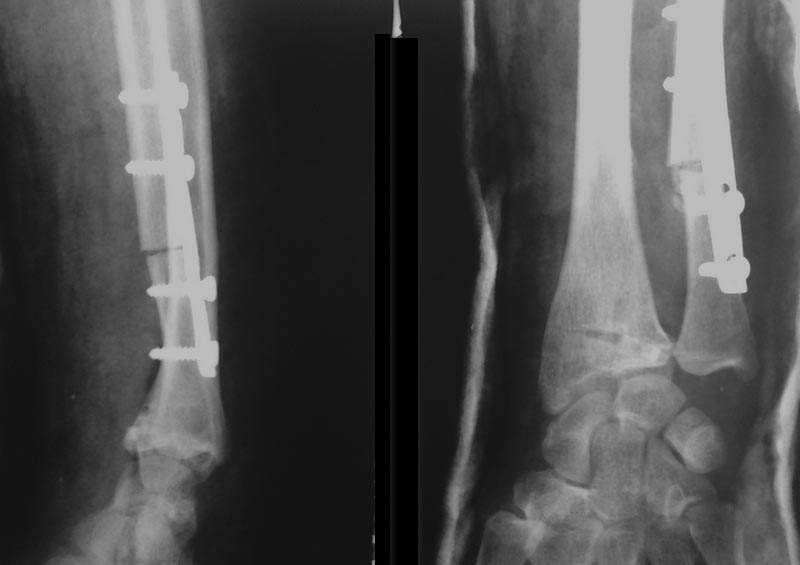

Мы для оценки луче-локтевого соотношения делаем снимок контрлатеральной конечности, можно простой оценкой определить объем резекции, можно и схему на кальке сотворить. Главное больше нужного не выбрать.Остеотомию выполняем осциллирующей пилой, можно и остеотомом с предварительным насверливанием тонким сверлом во избежание раскола.Укорочение локтевой кости способно устранить локтевой импинджмент синдром\Ulnar Impaction Syndrome\, который причиняет больше проблем пациенткам, чем косметический дискомфорт.В приложении послеоперационный снимок.

дабы не быть голословным.

Замещение дефектов НЕ выполнялось. Внешняя иммобилизация НЕ применялась. Полная функция с первых суток после операции. Таких примеров (имеется ввиду несращения и псевдоартрозы)- десятки.

К сожалению функцию по рентгенограммам оценить сложно. Однако если учитывать радио ульнарный индекс, то он перед операцией приблизительно +4 +5 мм ( в связи с тем что не известен масштаб приведенных снимков), после операции похоже на ноль-вариант, а на последних снимках похожи снова +2 +3 мм. Угол наклона суставной поверхности не сильно изменился, радио ульнарный угол стал немного получше. Однако мне кажется , сказалось не то смещение которое было до Вашей операции, а отсутствие адекватное реабилитации. И хотелось ба увидеть оценку функции до и после лечения с помощью опросников DASH, ну или MAYO SCORE....

Случаи малосравнимые. У ваших Р-граммах имеется большой дистальный отломок лучевой кости и стоит прилично - небольшая лучевая девиация и укорочение. Репозиция простая, фиксация отломка таких размеров легко и надежно выполняется пластиной из волярного доступа. В обсуждаемом примере дистальный отломок очень короткий и хорошей фиксации пластиной из переднего доступа не получится - слишком мало винтов через него пройдет. Учитывая давность травмы и пороз кости, высока вероятность, что винты постепенно прорежутся, отломок просядет. К сожалению я с этим сталкивался. Подчеркиваю, что речь идет о несвежих случаях

В представленном примере и произошло оседание дистального отломка, что видно при сравнение радио-ульнарного индекса, даже после действительно хорошей репозиции.